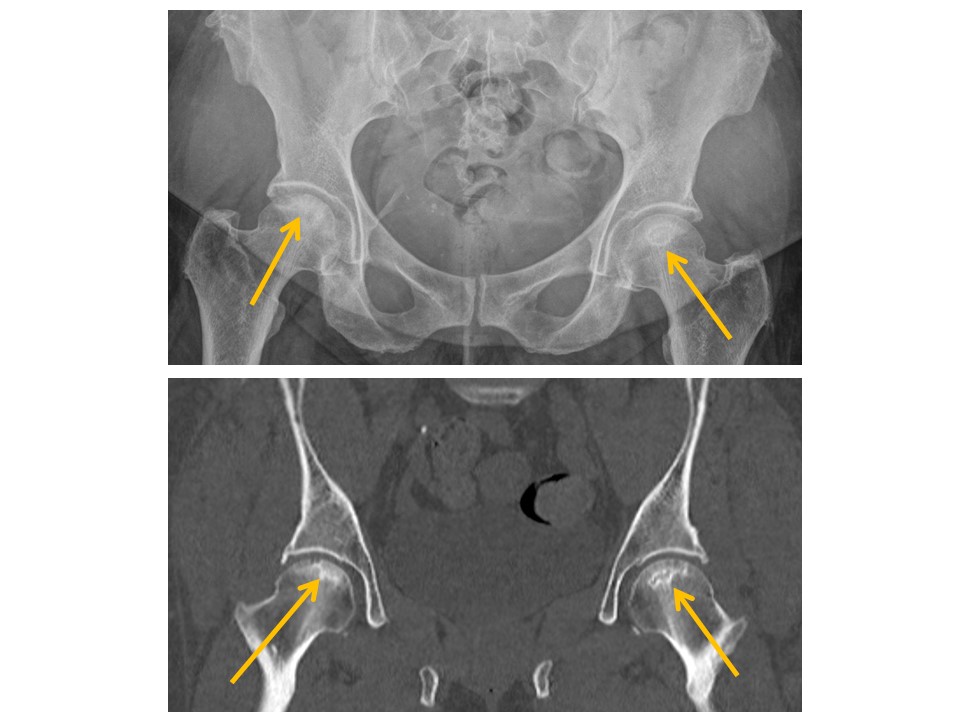

There is osseous prominence at the lateral femoral head/neck junctions. [Yes/No]

There are fractures of the femoral neck, intertrochanteric region, or subtrochanteric region. [Yes/No]

The trabecular pattern of the proximal femurs is abnormal. [Yes/No]